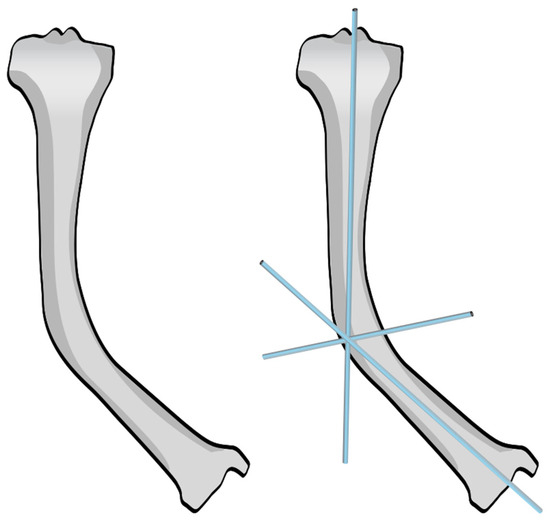

2.4. Reaming and Nail Insertion

Once the osteotomy is complete, the two bone segments can be reduced to ensure proper alignment (Figure 7a). Reaming can then be performed retrograde into the proximal bone segment through the osteotomy site, and antegrade into the distal bone segment (Figure 7b–d). Under fluoroscopy, external K-wires or SLIM nails are used to measure the required nail length, which is subsequently verified with the actual nail before insertion. Finally, the nail is inserted, positioned centrally in the canal, and advanced until the proximal threads anchor in the epiphysis (Figure 7e). The technique described above and in Figure 7 describes the retrograde approach. In cases with mild deformity (less than 20 degrees in the coronal or sagittal plane) a mini invasive percutaneous osteotomy could be performed, and in such cases, an antegrade approach could be used, in which the insertion of the guide wire, reaming, and insertion of the SLIM nails are all performed through the proximal entry points.

Figure 7.

Intramedullary reaming and SLIM nail insertion. Blue arrows indicate the direction of reaming and nail insertion. (a) Osteotomy is complete. (b) Lateral view of proximal reaming via the osteotomy site. (c) AP view of proximal reaming via the osteotomy site. (d) AP view of distal reaming via the osteotomy site. (e) Insertion of the SLIM nail.